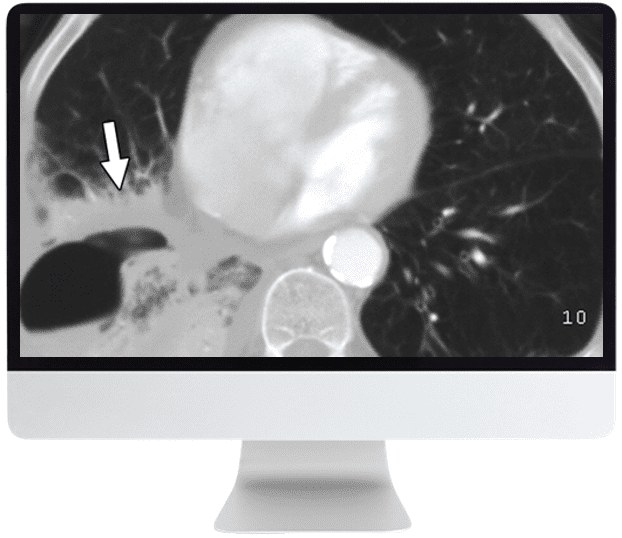

- Chest — Malignancies and Lung-RADS; Nodular Lung Disease: An Approach; Diffuse Lung Disease; Lymphatic Drainage of Thoracic Metastases; Mediastinum